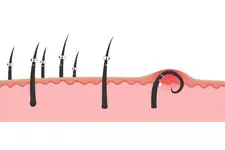

Kuyruk sokumu kıl dönmesi, tıbbi literatürde "pilonidal hastalık" olarak bilinen bir durumdur. Bu hastalık, kuyruk sokumu bölgesinde kılların derinin altına doğru büyüyerek iltihaplanmasına ve enfeksiyon oluşturmasına yol açar. Genellikle genç erkeklerde daha sık görülmekle birlikte, kadınlarda da ortaya çıkabilir. Bu makalede, kuyruk sokumu kıl dönmesinin belirtileri, nedenleri ve tedavi yöntemleri üzerinde durulacaktır. Belirtiler Kuyruk sokumu kıl dönmesinin belirtileri genellikle şu şekildedir:

Bu belirtiler, hastalığın evresine göre değişkenlik gösterebilir. Başlangıçta hafif rahatsızlık hissedilse de zamanla belirtiler şiddetlenecek ve yaşam kalitesini olumsuz etkileyecektir. Nedenleri Kuyruk sokumu kıl dönmesinin kesin nedeni henüz tam olarak anlaşılamamıştır. Ancak, bazı faktörlerin hastalığın gelişiminde etkili olduğu düşünülmektedir: